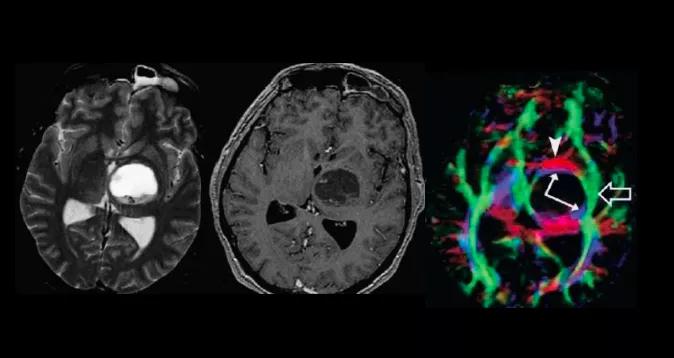

左侧颞部脑膜瘤DTI示左侧神经纤维束受压移位,但连续性完整,符合模式I

左侧额叶低级别胶质瘤,低灌注,左侧额叶白质纤维破坏,无法看出走行,符合模式IV